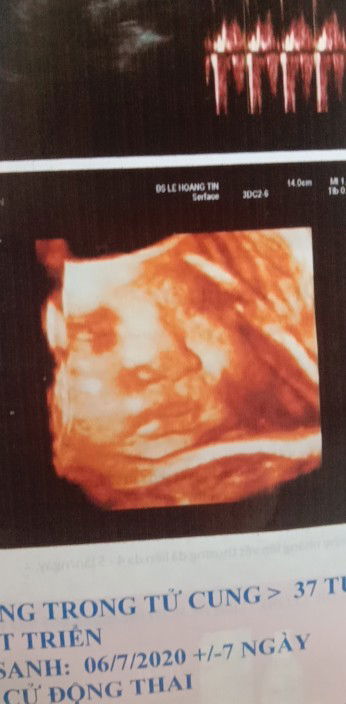

Preggers